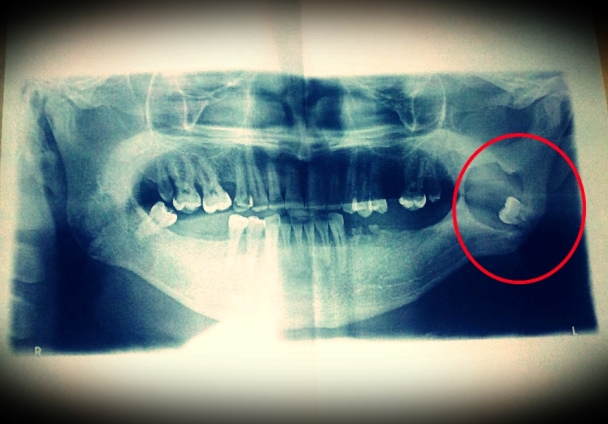

Segundo Francineide, o homem de nome Severino Ramalho Patrício, residente no Sitio Varjota, faz um tratamento dentário há mais de quatro anos, e atualmente (em media um ano) o seu caso se agravou, por já está sendo mal atendido em Milagres, Severino buscou atendimento na Secretaria de Saúde de Brejo Santo, a mesma através do CEO o encaminhou de volta para Milagres.